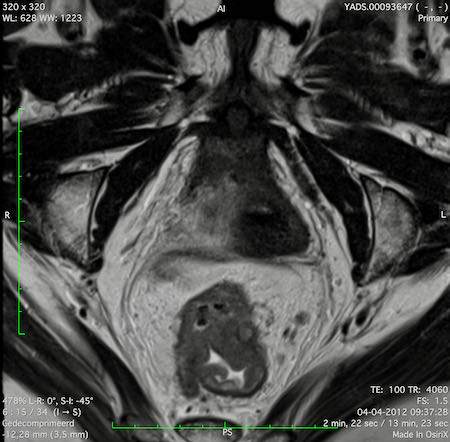

Hình ảnh

Các hình ảnh được cung cấp cho thấy ung thư biểu mô tế bào nhẫn với tình trạng dày lan tỏa thành trực tràng, hình ảnh bia bắn điển hình, và sự xâm lấn mỡ mạc treo trực tràng.